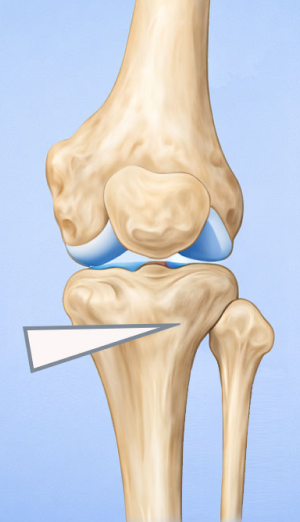

근위경골 절골술(휜다리 교정술)

High Tibial Osteotomy (HTO)무릎 아래 뼈인 경골(정강이뼈)의 윗부분(근위부)을 절골하여 다리 정렬을 바로잡는 무릎 교정 수술입니다.

관절면과 평행하게 절골하여 각도를 교정

정강이 위쪽 뼈(경골 근위부)를 절골합니다.

약간 벌리거나 닫아서 다리축을 “일자에 가깝게” 교정해서 닳은 안쪽 무릎의 부담을 줄이고 통증 감소 및 기능 향상을 유도합니다.

절골한 부위는 금속판(plate)으로 고정합니다.

시간이 지나면 뼈가 붙습니다.